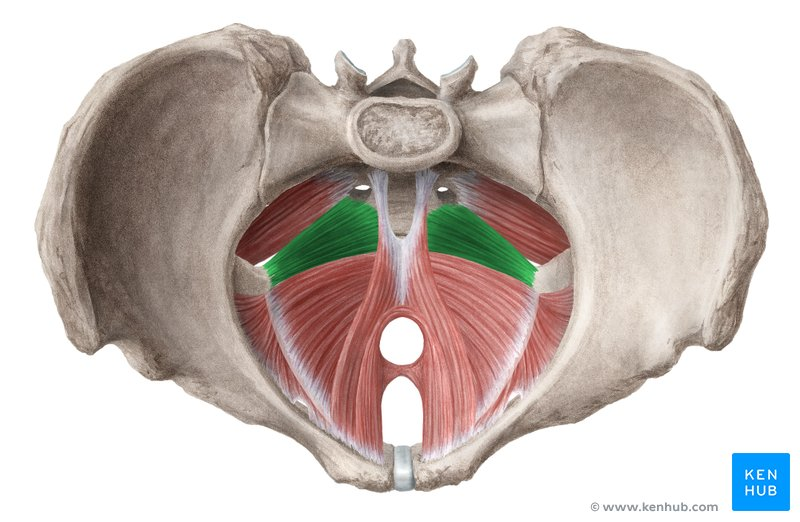

m levator ani

coccygeus